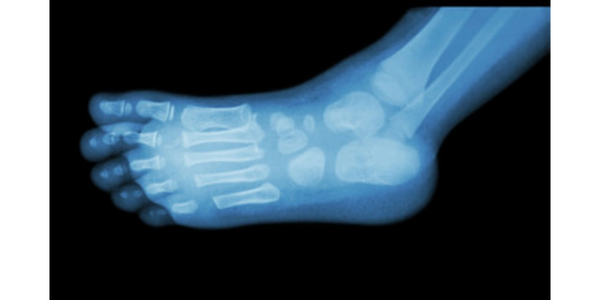

- the x-ray of a child's foot can reveal their age

- many bones in children's feet start off as cartilage

- the ossification centre of the navicular doesn't emerge until around the age of 3 (meaning you won't spot it on x-ray)